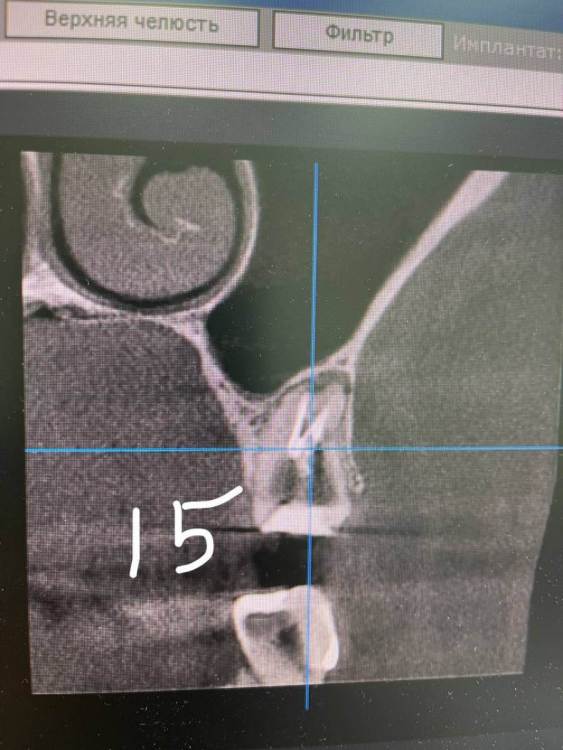

TIGER Опубликовано 8 мая, 2023 Автор Поделиться Опубликовано 8 мая, 2023 Всем привет!планировал удаление,но во время синуса решил использовать фрагмент как клин для стабилизации болта,в итоге совершил ошибку с более медиальной позицией 26,ибо шаблон не изготовил....через 5 мес одел времяхи,т.к будет тотал Ссылка на комментарий